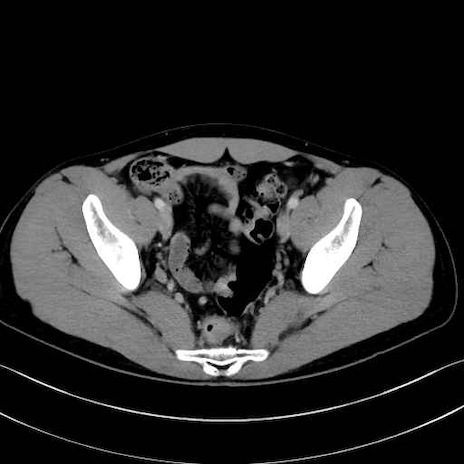

2. 腸腰筋群と骨盤底筋

大腰筋 (Psoas major)

腸骨筋 (Iliacus)

肛門挙筋 (Levator ani)